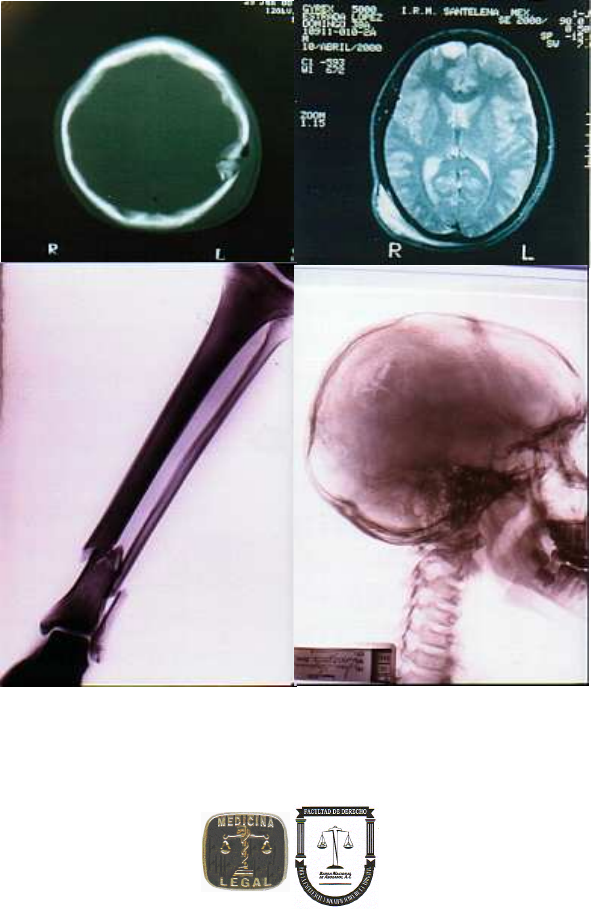

Puede presentarse fracturas de cráneo con hundimiento

por debajo de la “línea del sombrero”

a) sobre el segmento superior del cuerpo

presenta fracturas conminutas conocidas como el signo de la bolsa de las

nueces, con hundimiento y aspecto de telaraña. Las lesiones craneales se

encontrarán por encima de la “línea del sombrero” (punto craneométrico

estefanion)

b) impacto sedente: incrustación de las alas menores del esfenoides y de la

apófisis crista galli sobre el encéfalo por la transmisión de la energía a estos

niveles

c) sobre el segmento inferior del cuerpo: introducción de la columna a la

bóveda craneal y afectación encefálica, con fracturas del astrágalo y el tercio

medio de las piernas